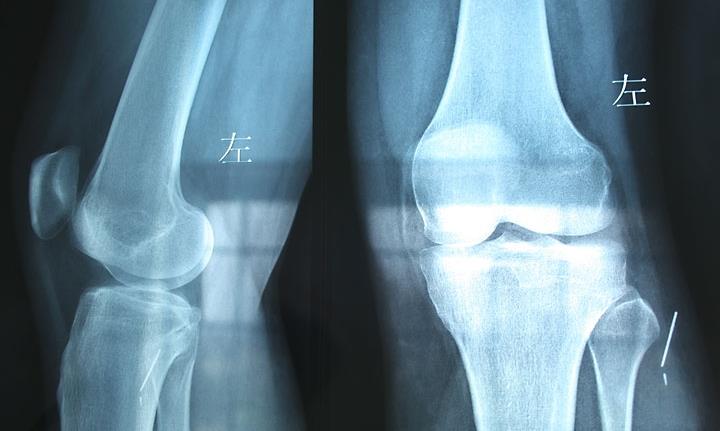

29日上午,在临沂市第四人民医院外一科病房,记者见到了王女士,她刚刚于7月28日做完手术。据了解,王女士是兰山区人,一周前她乘电动三轮车外出。行至市区某路段时,一私家车将王女士乘坐的电动三轮撞翻。随后王女士来到市第四人民医院拍片检查。但检查的结果让王女士感到很意外:骨骼等组织均没事,但X片却显示左膝关节外侧皮下有一个几厘米长、金属样的物体。王女士感到很奇怪,自己没有做过手术,也没有被扎过,体内怎么会有金属样的东西呢?于是王女士又重新拍了个片,结果和此前的一样。

这个金属样的物体到底是什么?“隔皮猜瓜”谁也弄不清楚,医生称必须做手术才能知晓。7月28日,王女士被推上手术台。参与手术的刘大夫发现,位于王女士左膝关节外侧皮下约1厘米处有一缝衣针。“缝衣针长约5厘米,在她体内已断成了两截,一截长4厘米,一截长1厘米。”刘大夫说,缝衣针被包在脂肪组织内,属于炎性包裹。刘大夫随后将缝衣针剥离取出。